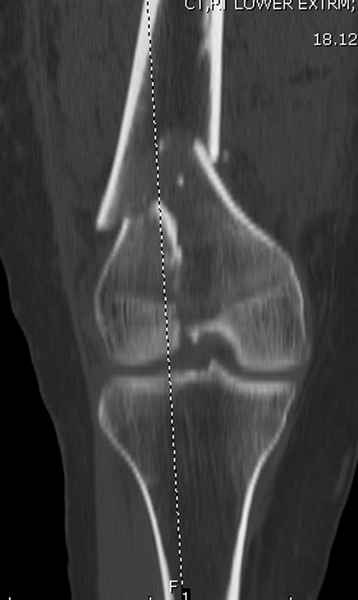

Вложение не в текстовом формате было извлечено…

Имя     : distal femur crm 3.jpg

Тип     : image/jpeg

Размер  : 14063 байтов

Описание: отсутствует

Url     : http://weborto.net:8080/pipermail/ortho/attachments/20081001/5646c87e/attachment-0014.jpg